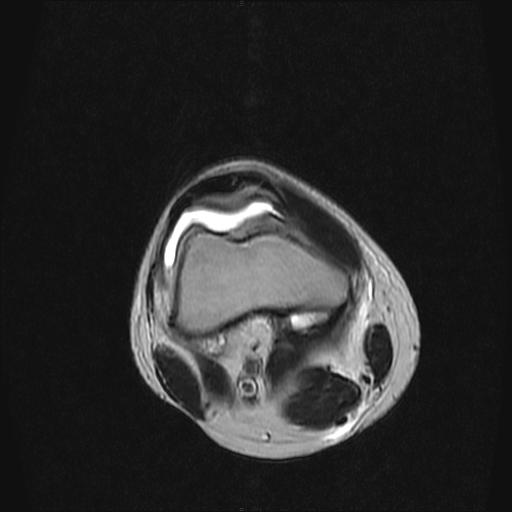

40岁男性,右膝关节外伤,x光平片示,髁间隆突撕脱骨折。

2、外侧半月板后角撕裂;

3、关节腔积液。

半月板1-2级损伤   前交叉韧带撕裂伤   关节腔少量积液  诸骨未见新鲜外伤性改变

半月板1-2级损伤   前交叉韧带撕裂伤   关节腔少量积液

1、内侧副韧带撕裂;

3、滑膜炎伴关节腔积液。

1、前交叉韧、内侧副韧带撕裂;

3、关节腔积液。4、髁间脊撕脱骨折。

2、前交叉韧带撕裂;